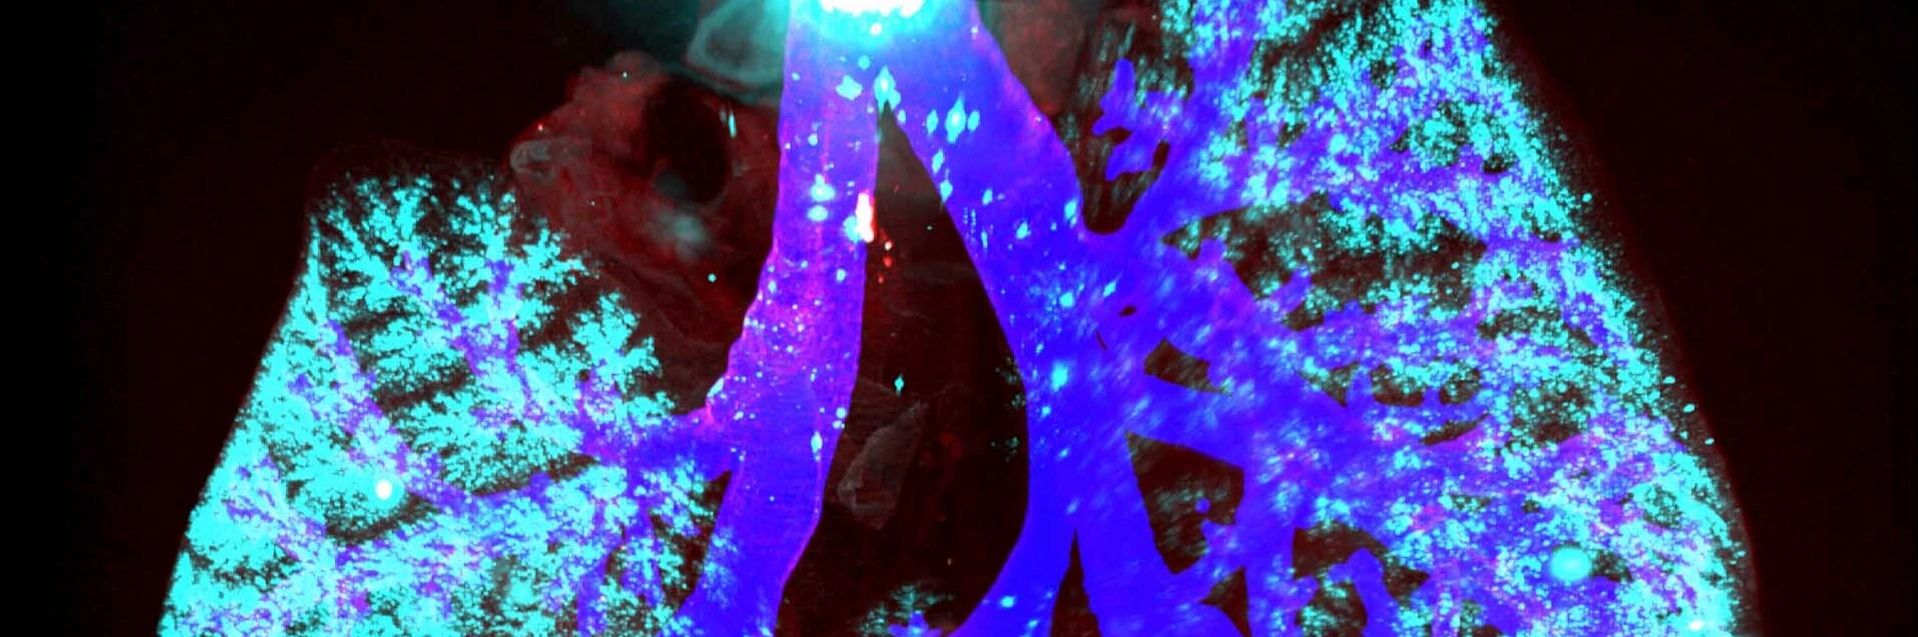

Lung Health and Immunity

Many environmentally triggered lung diseases are still considered incurable. We explore the immunological mechanisms underlying chronic lung diseases such as COPD, lung fibrosis, asthma, lung cancer and the complications following lung transplantation. We want to translate our findings into preventative and therapeutic approaches for patients.

Many environmentally triggered lung diseases are still considered incurable. We at the Institute of Lung Health and Immunity (LHI) explore the immunological mechanisms underlying chronic lung diseases such as COPD, lung fibrosis, asthma, lung cancer and the complications following lung transplantation. We want to translate our findings into preventative and therapeutic approaches for patients.